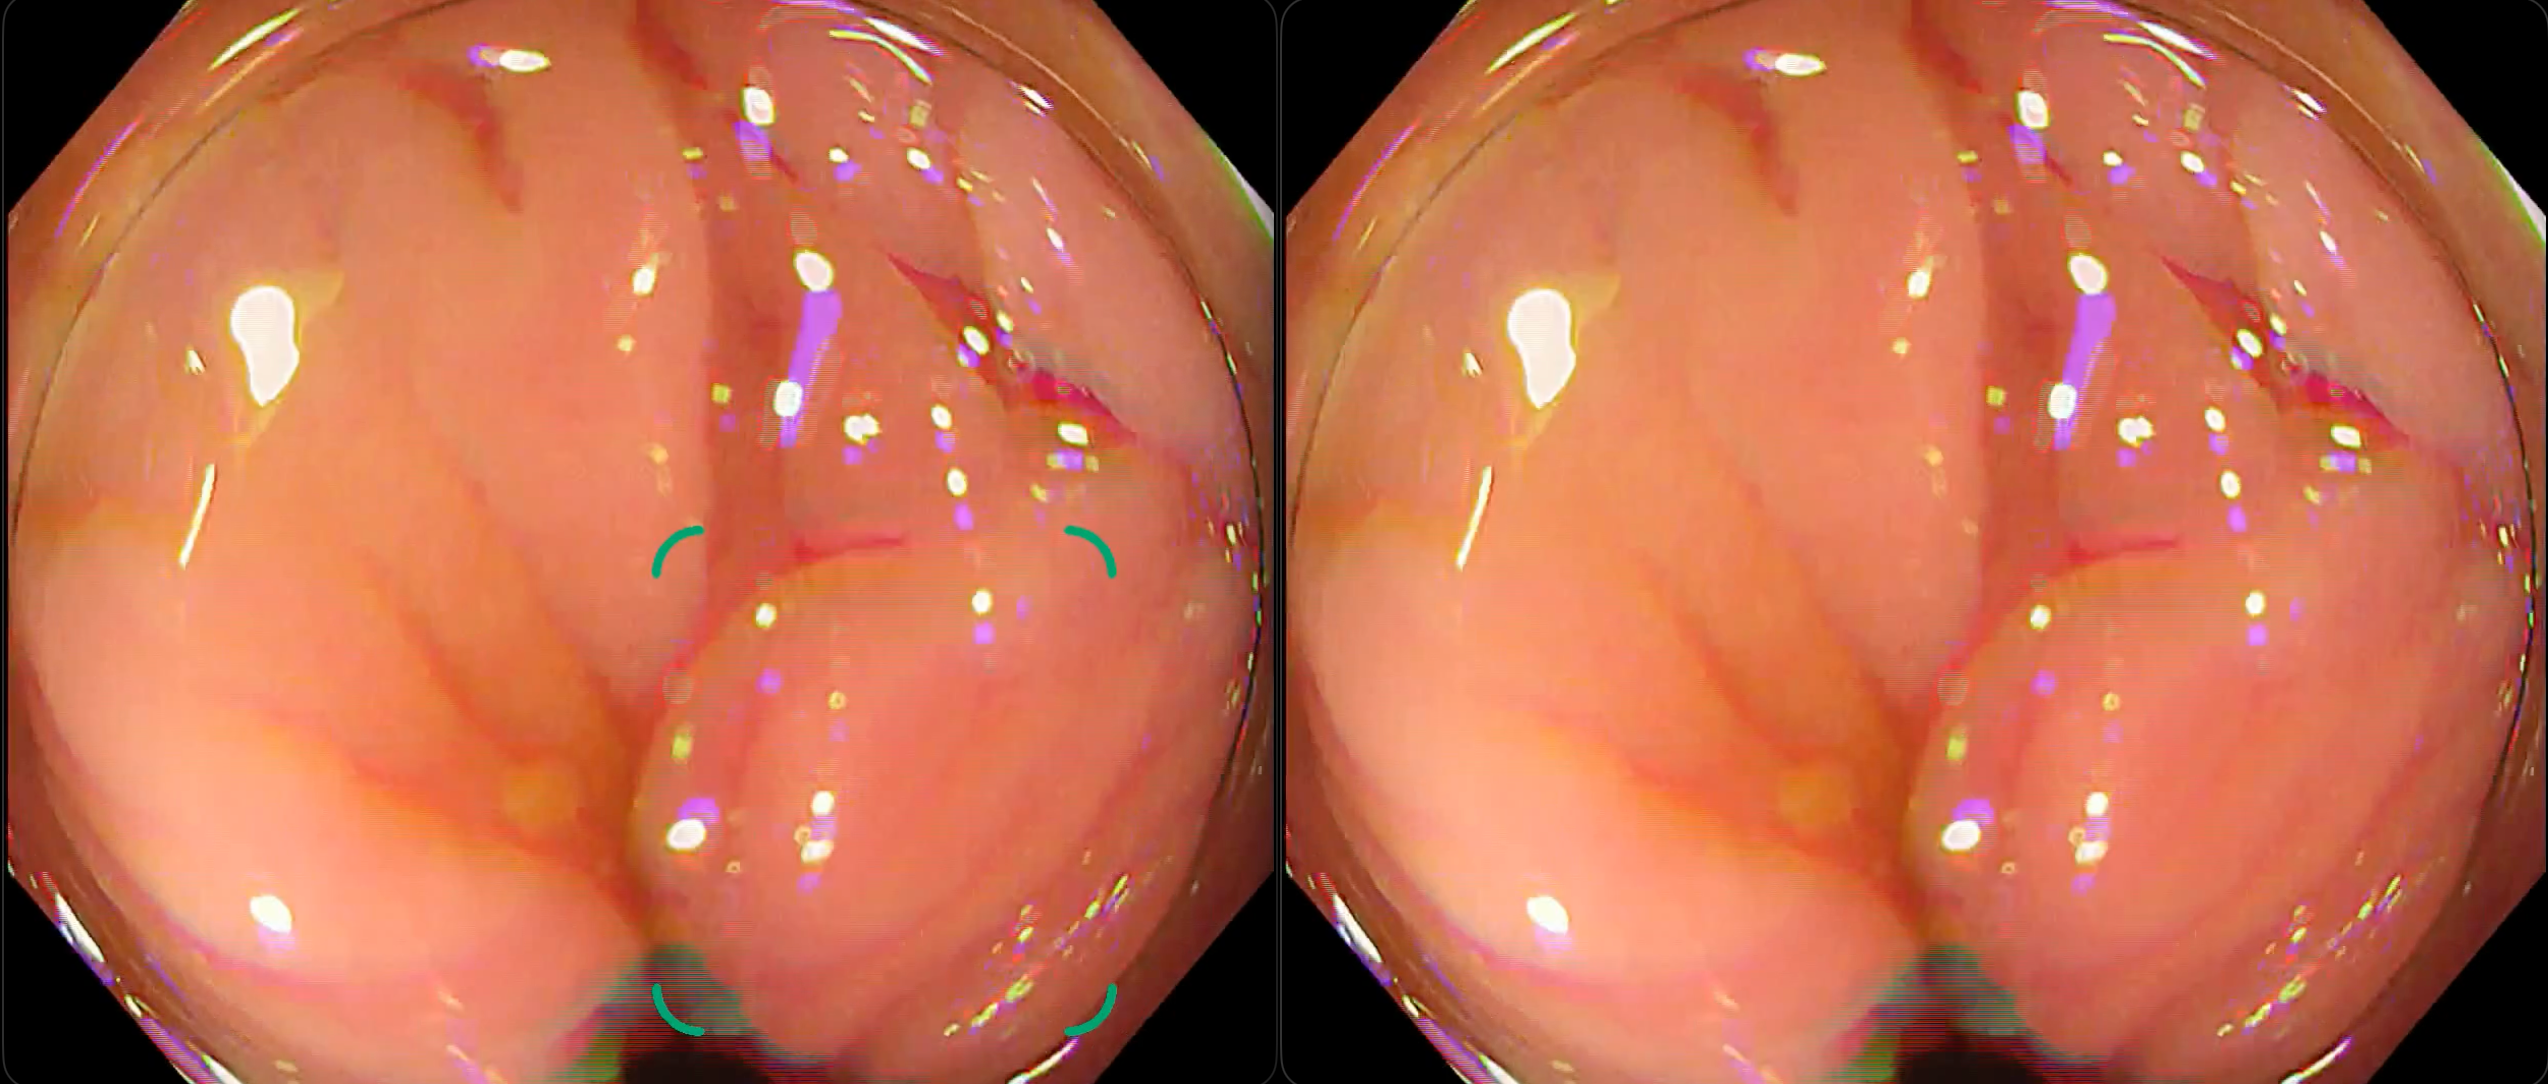

【検出事例】新旧モデル比較(左:旧モデル、右:新モデル)

① 残渣による偽陽性が改善した例

② ひだによる偽陽性が改善した例

※いずれの検出例もイメージであり、実際の製品表示とは異なる場合があります。